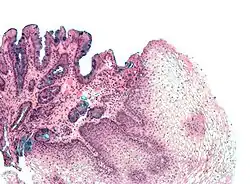

A metaplasia do esôfago de Barrett é bastante visível através da endoscopia digestiva alta. No exame pode ser notada uma lesão de "cor salmão" ou "cor vermelho-róseo". O médico que realiza o exame endoscópico recolhe amostras da lesão esofágica (biópsia).

Estas amostras são analisadas sob microscópio para determinar se as células são de natureza gástrica ou intestinal[5]. A metaplasia intestinal do esôfago de Barrett é geralmente identificada com a ocorrência de células caliciformes no epitélio. A presença das células metaplásicas intestinais é necessária para que o diagnóstico da doença seja confirmado.

Biópsia

O esôfago de Barrett é caracterizado por uma modificação no epitélio do órgão. Na doença, ocorre a presença de epitélio colunar na porção inferior do esôfago, substituindo o epitélio escamoso normal do esôfago. Esta transformação do epitélio é um exemplo de metaplasia. Apesar de o epitélio colunar ser capaz de suportar melhor a ação erosiva das secreções do estômago; esta metaplasia confere um risco aumentado de câncer no esôfago do tipo adenocarcinoma.[6]

As células colunares metaplásicas podem ser de dois tipos: gástricas (similares às do estômago, que não são tecnicamente um esôfago de Barrett) ou intestinais (similares às células dos intestinos). Uma biópsia da área afetada geralmente irá apresentar uma mistura de ambos os tipos. A metaplasia intestinal confere um risco maior de malignidade.